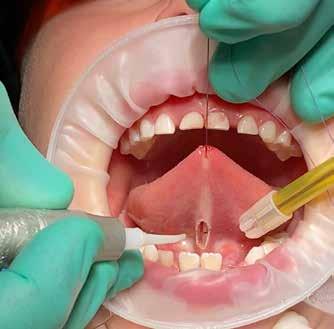

S.V. Paziente di tre anni di sesso maschile, in III Classe scheletrica lieve, con open-bite, deglutizione atipica, contrazione dell’arcata superiore, tendenza alla III Classe. Alla prima visita il paziente presentava un evidente frenulo vestibolare corto, a tetto labiale che, trazionando il labbro superiore, tendeva a ischemizzarsi insieme alla papilla retroincisiva.

In situazioni simili si potrebbe anche attendere ma, poiché si rendeva necessaria una terapia ortodontica, si è proceduto ad eseguire una frenulectomia e il giorno stesso è stato consegnato al paziente l’apparecchio elastodontico per la correzione della malocclusione. Lo scudo vestibolare dell’apparecchio ha contribuito alla guarigione del frenulo stesso determinando una trazione continua sul labbro superiore.

La sequenza terapeutica ha previsto i seguenti step:

• frenulectomia laser;

• terapia elastodontica al fine di ripristinare la corretta crescita scheletrica e dentale.

Fig. 4

Fig. 5 > Immagine intraorale frontale.

Fig. 6 > Immagine intraorale laterale destra.

Fig. 7 > Immagine intraorale laterale sinistra.

Fig. 8 > Dettaglio del frenulo labiale superiore corto.

Figg. 9-11 > Intervento di frenulectomia con laser a diodo.

Figg. 12, 13 > Controllo dopo ventiquattro ore.